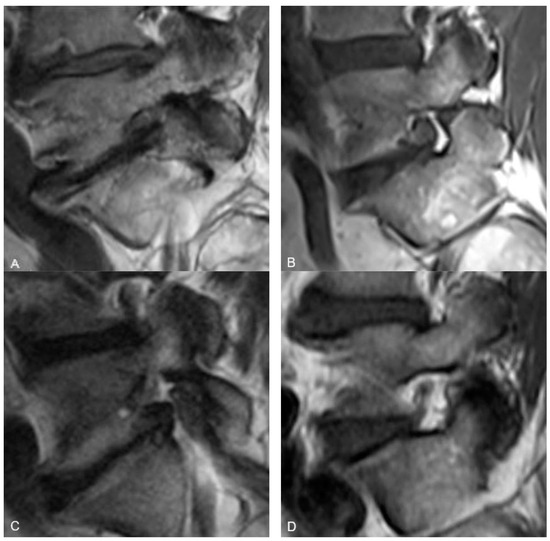

For qualitatively determining the presence and location of vessels within the neural foramen, the reviewers were instructed to use the same MRI slice that they used to judge the foraminal fat. A convincing punctate low signal intensity structure next to the nerve root (either antero-superiorly or postero-inferiorly) on the sagittal T1 sequence was considered a vessel (Figure 2). Vessels were considered present when seen but considered “Not Applicable” when not seen because in cases where there was no fat (“None”) in the neural foramen, it would not be possible to see a vessel, and because many vessels may be too small to see within the resolution limits of the MRI.

Figure 2.

Representative sagittal T1w MR images of the L5-S1 neural foramen demonstrating foraminal vessels (arrows) in the antero-superior foramen (A) and postero-inferior foramen (B).